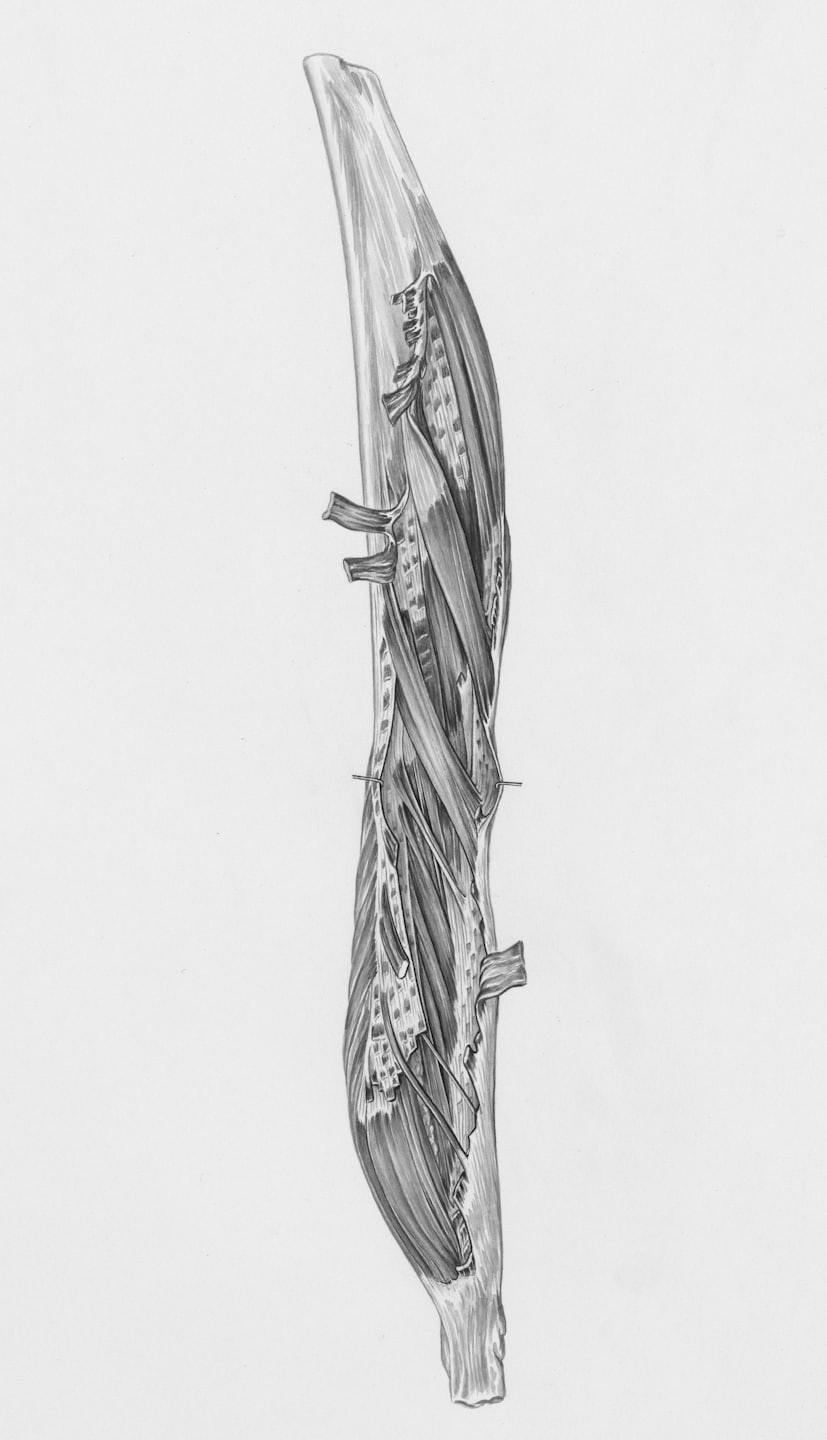

El desarrollo de unos brazos masivos y funcionales depende de la manipulación precisa de los momentos de fuerza. En este análisis de ingeniería, diseccionamos la biomecánica de flexión y extensión de codo para asegurar que cada grado de movimiento genere la máxima tensión mecánica, protegiendo siempre la salud de tus tendones.

Aplicamos cálculos de momentos de fuerza para maximizar el crecimiento muscular saludable.

Protección Tendinosa

Estrategias para fortalecer tendones y prevenir lesiones durante el entrenamiento intenso.

Estudio detallado de la flexión y extensión del codo para mejorar la función muscular.

Aprende cómo manipular momentos de fuerza para maximizar la flexión de codo.

Descubre estrategias para mejorar la extensión del codo y proteger tendones.

Aquí encontrarás imágenes que ilustran la biomecánica y técnica para maximizar la hipertrofia muscular.